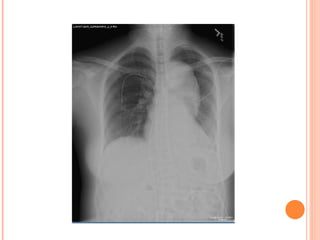

CXR PITFALLS   abnormal in 80-90% of cases Mediastinal widening- in 75% “ Calcium sign Aortic double density Disparity in caliber between ascending and descending aorta Localized bulge on the aorta Obliteration of the aortic knob NG tube, trachea or ETT displaced to the right Pleural effusions- common and usually on the left